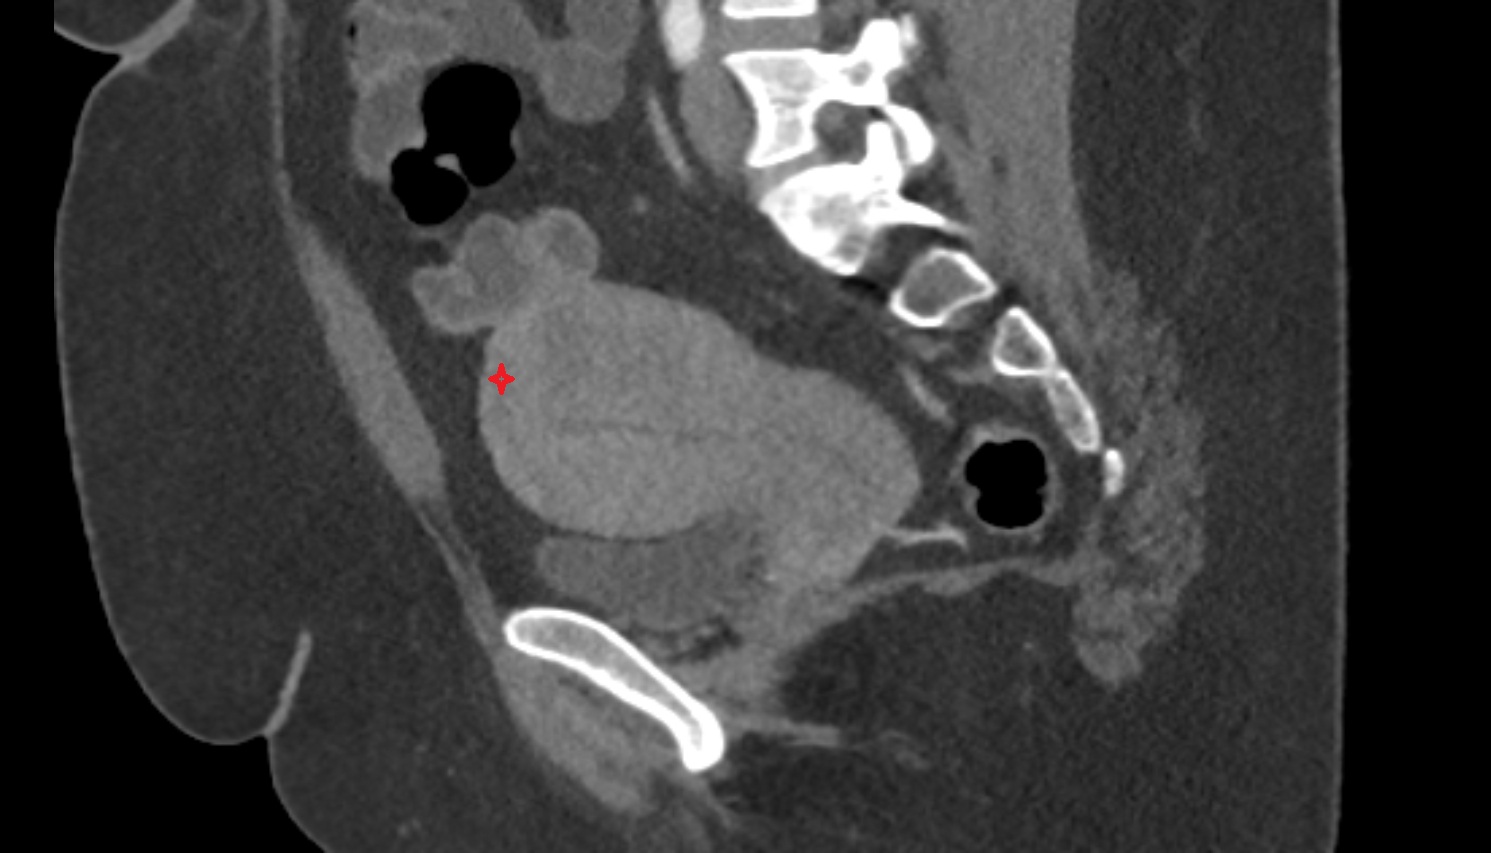

- Uterus

- Body of uterus

- Fundus of uterus

- Cervix of uterus

- Isthmus of uterus

- Vagina

- Rectum

- Urinary bladder

- Vesicouterine pouch

- Rectouterine pouch (pouch of Douglas)